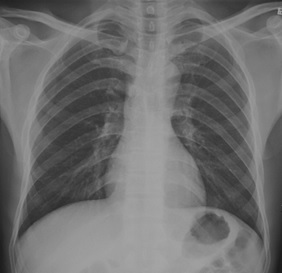

试题:根据下图请做出正确诊断

A.正常胸片

B.肺门淋巴结肿大

C.肺炎

D.主动脉型心(靴型心)

正常胸片